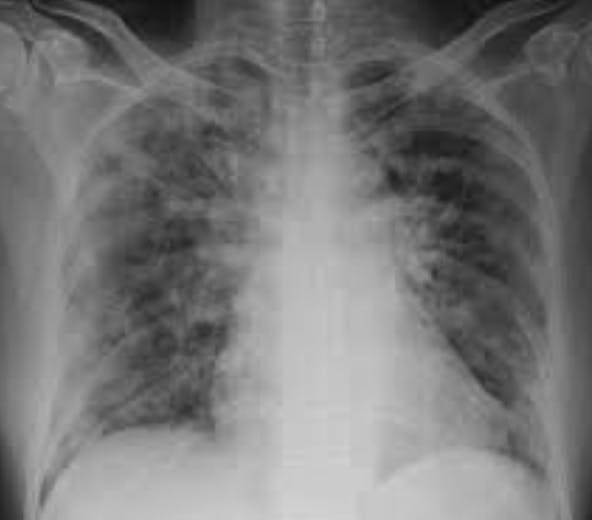

Since he had pneumonia, I pictured his lungs as a hotbed of inflammation harboring similar crusty, oozing lesions whose thick membranes and inflammatory exudate barricaded the transfer of oxygen to the bloodstream. The lungs' delicate, lace-like, elegant air sacs (alveoli) become fiery, inflamed, and thicken as they fill with fluid and pus. I’m sure you have seen pus. Think of it in your lungs.

A pathologist would report it as metaplasia (the conversion of one type of cell to another), large clots, organizing infection, heightened inflammation, cell death, and a significant reduction in the lung’s capacity to do its job. Fine, but the words crud, swamp, and devastation came to my mind. The phrase, “The pox is on(in) him,” surfaced as my patient gulped for air.

If you have vaccine hesitancy or mask resentment, I ask you to picture the blisters of adult chickenpox and the lungs of the patients on the intensive care units. Would you want lungs that looked like that? I would guess not.